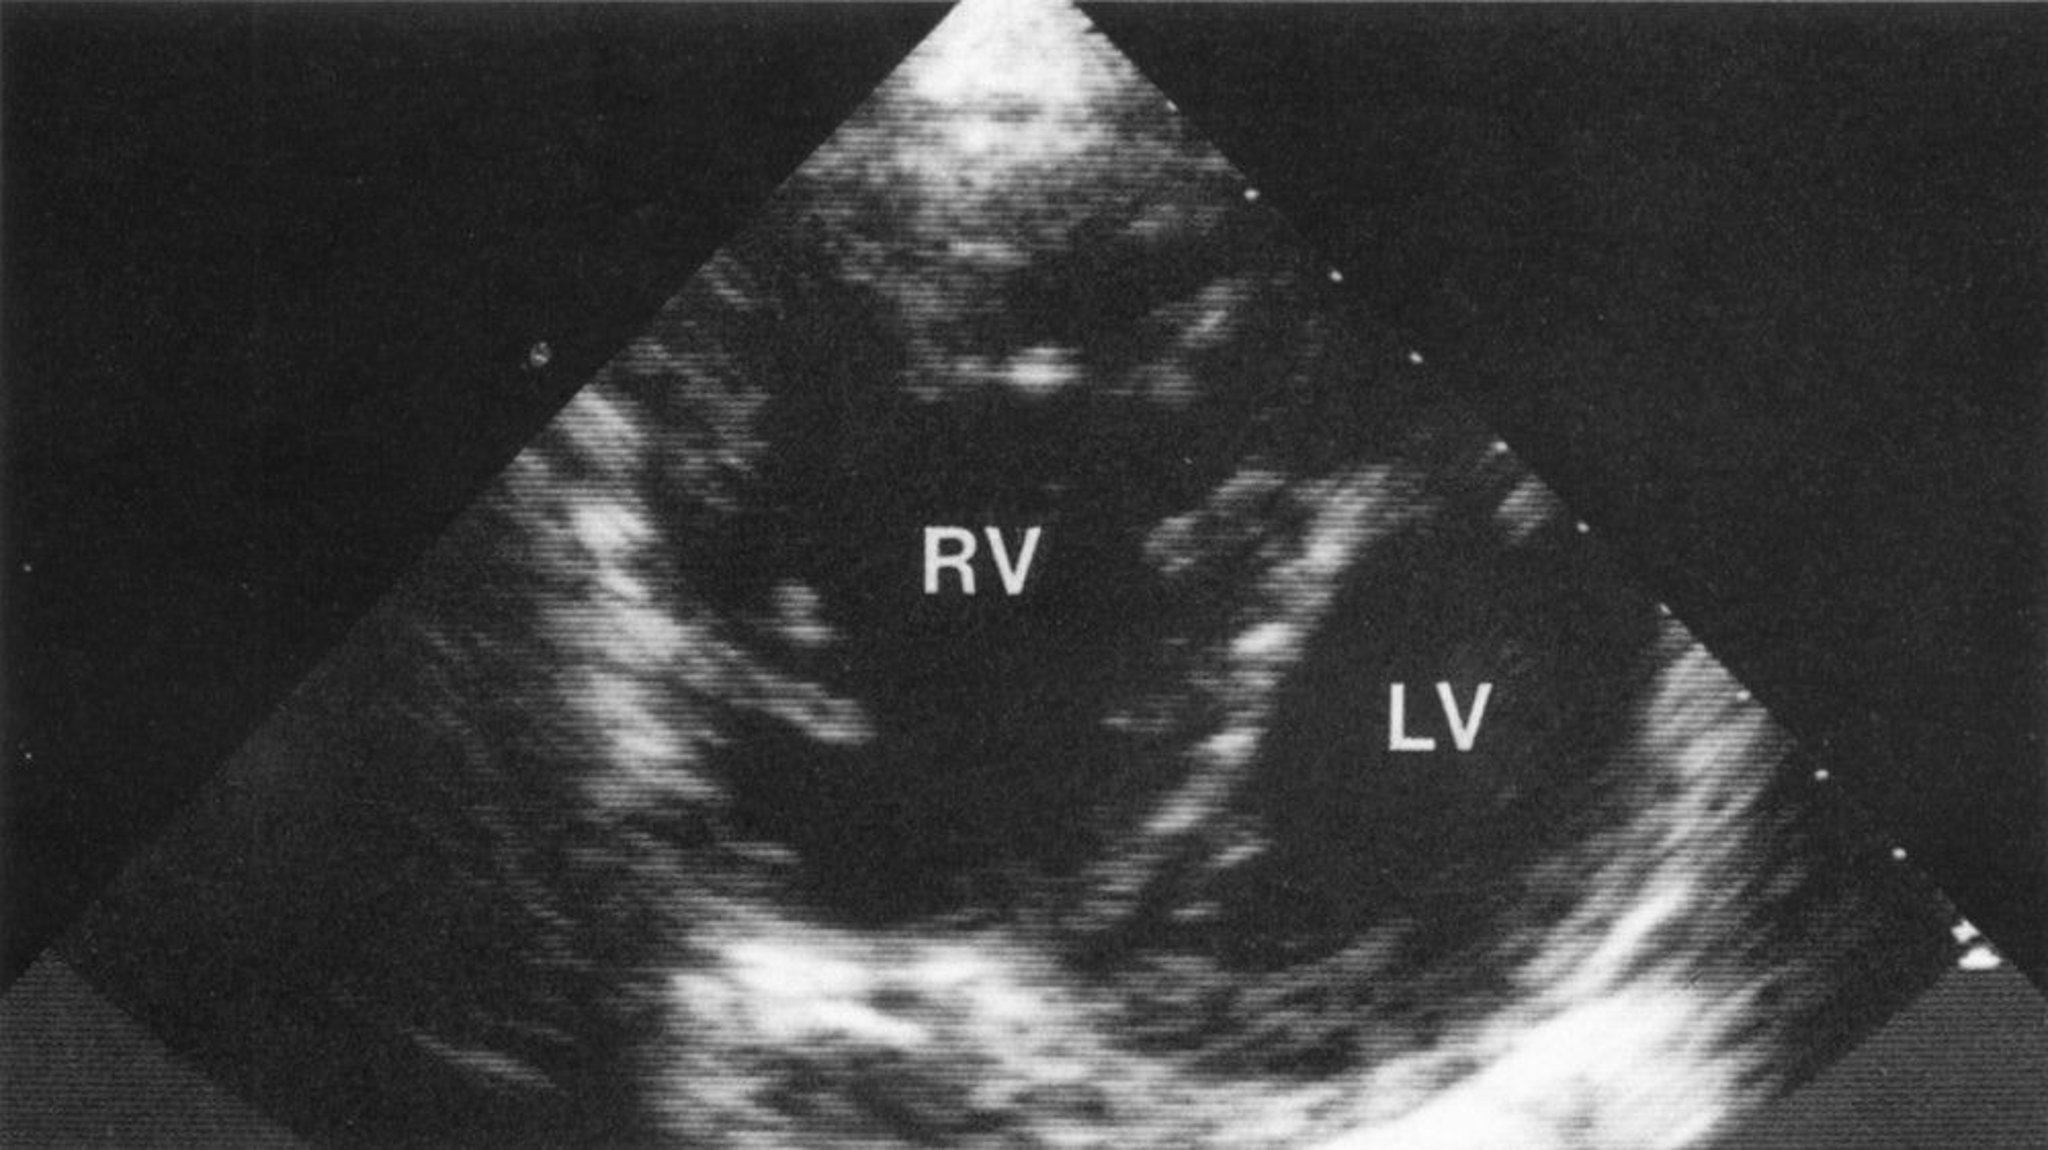

Cor Pulmonale (Echocardiogram)

Short-axis view demonstrating a markedly enlarged right ventricle (RV) with RV hypertrophy. Abnormal bowing of the interventricular septum into the left ventricle (LV) gives a characteristic D configuration of the LV, consistent with volume and pressure overload of the RV.